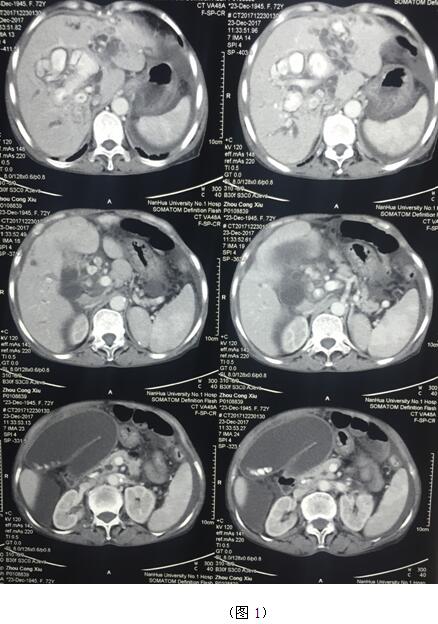

肝膽管結(jié)石疾病往往“鐘愛(ài)”貧困落后地區(qū)的病人,70多歲的周奶奶患全肝結(jié)石多年,由于家庭困難一直沒(méi)有得到有效治療,這個(gè)月病情惡化出現(xiàn)化膿性膽管炎并肝功能衰竭(圖1)。轉(zhuǎn)輾衡陽(yáng)市內(nèi)多家醫(yī)院,不是因高昂的治療費(fèi)用止步于院外,就是被以“病入膏肓”為由推脫出院。家屬經(jīng)過(guò)多方打聽(tīng)得知衡陽(yáng)市中心醫(yī)院是市里面的仁濟(jì)醫(yī)院,肝膽外科還是省級(jí)重點(diǎn)專(zhuān)科,家屬及病人懷著最后的希望來(lái)到了醫(yī)院肝膽外科。